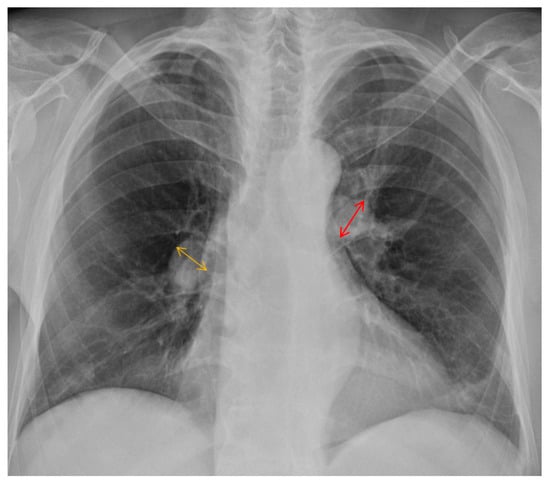

2. Case Presentation

| High-sensitivity troponin I | 48.8 pg/mL |

| N-terminal pro-brain natriuretic peptide | 4528 pg/mL |